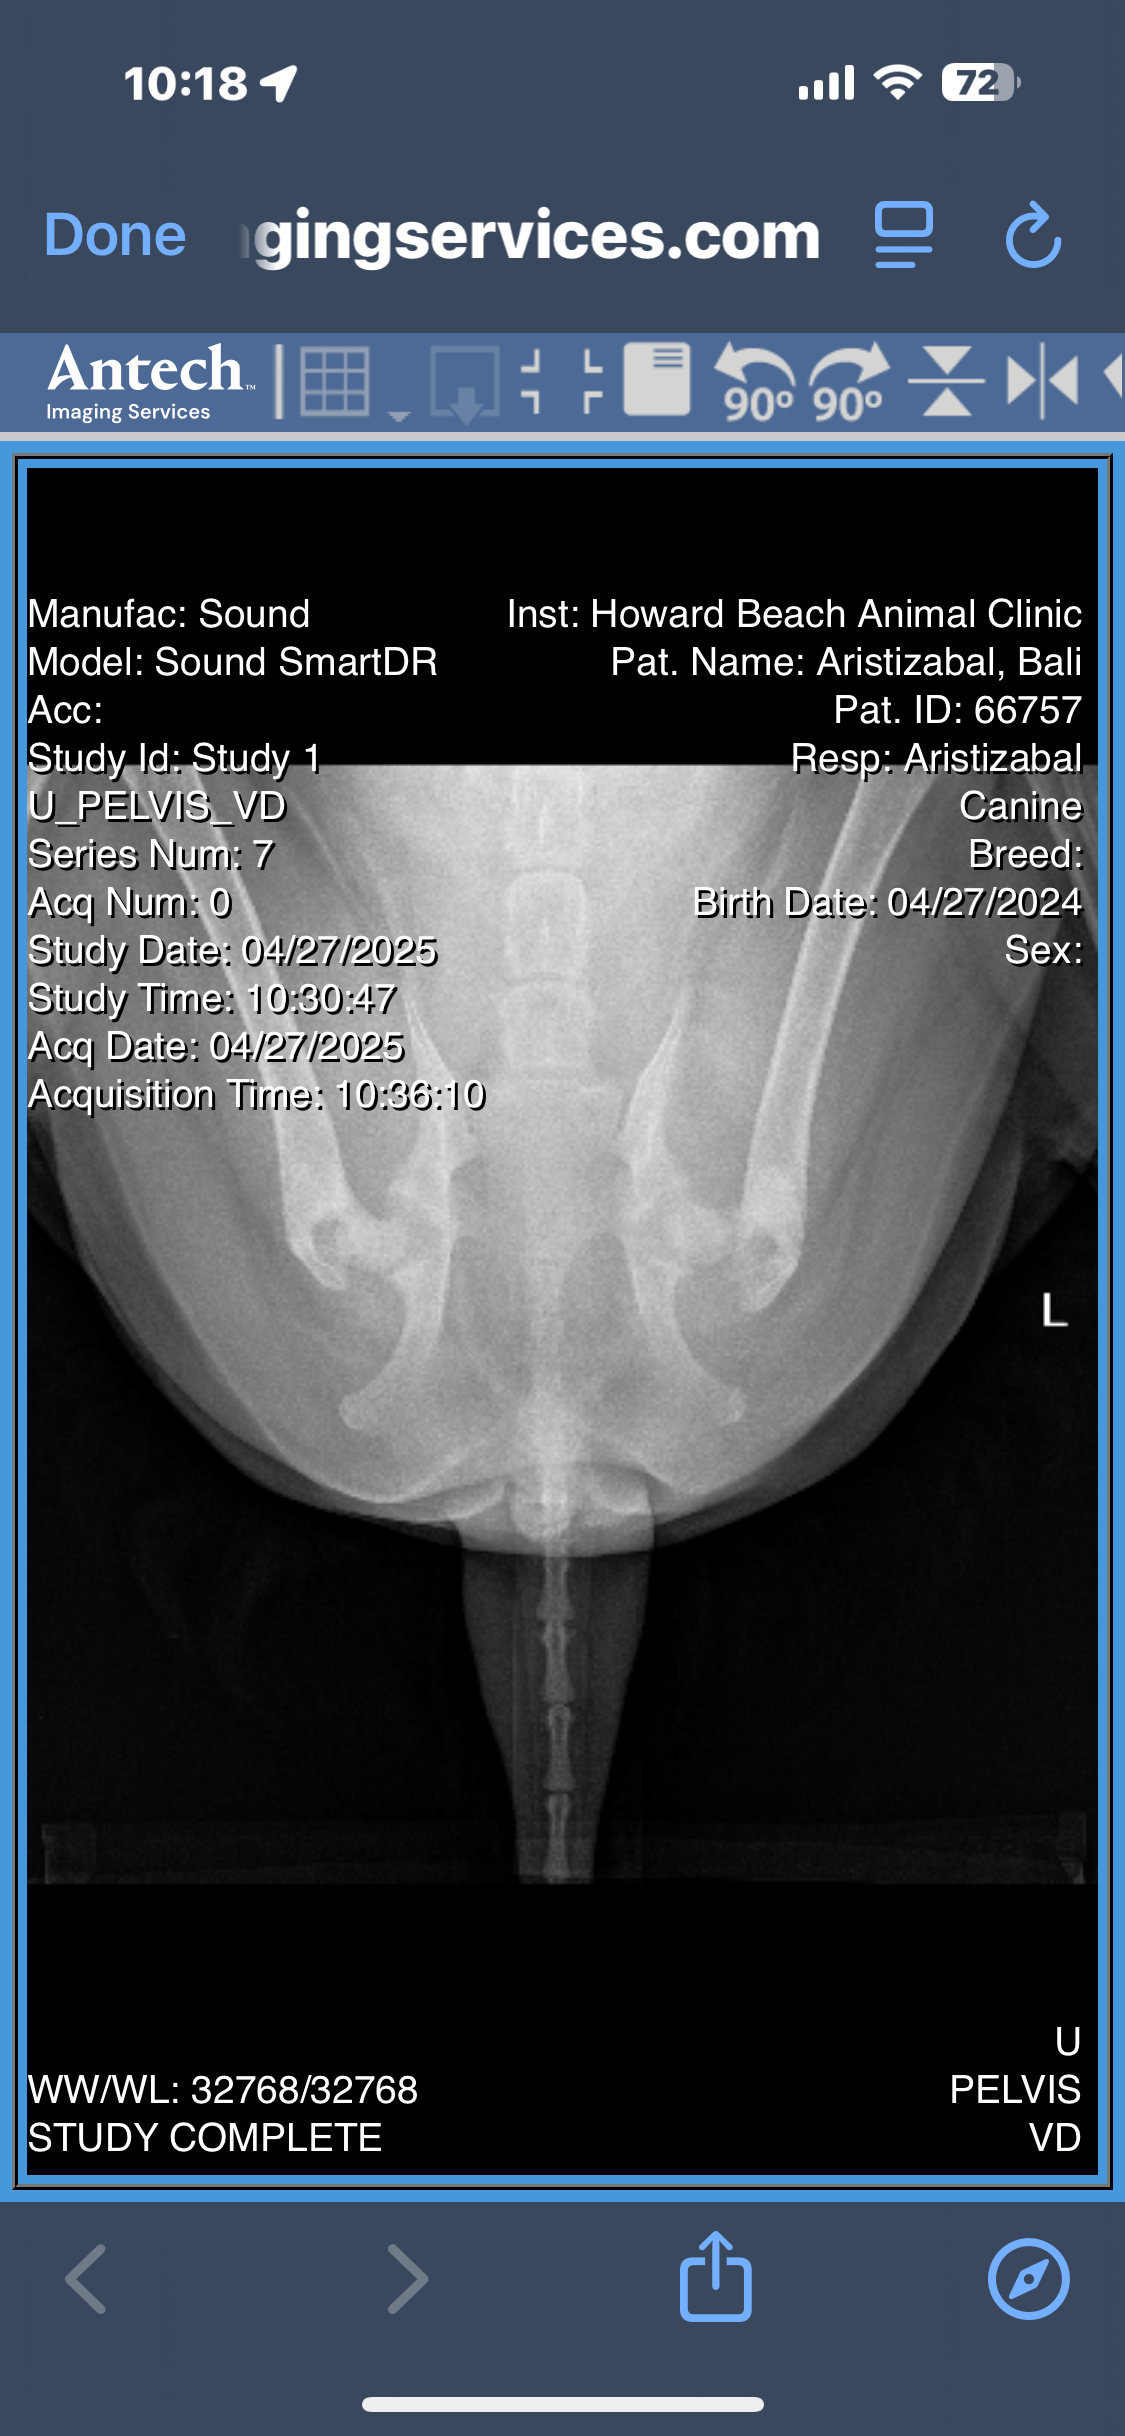

After months of limping, discomfort, and visits to the vet, Bali’s radiographs revealed multiple orthopedic issues:

• A minimally displaced fracture in her left femoral neck

• Severe bilateral hip dysplasia, more advanced on the left

• Osteoarthritis in both hips, with significant muscle atrophy

• Possible avascular necrosis of the femoral head or slipped femoral capital epiphysis

• And the concern of an underlying septic arthritis that hasn’t yet been ruled out